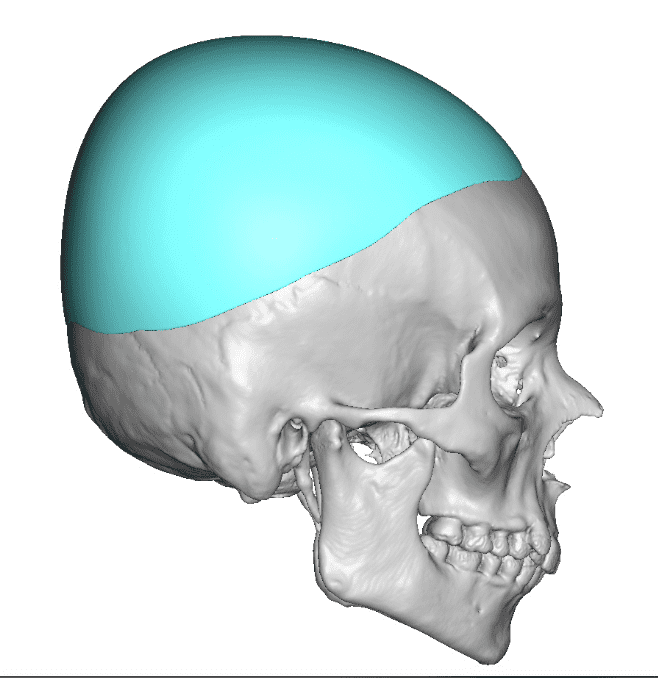

Desire for an improved head shape so that it looks rounder and not so peaked or sloped.

Placement of custom skull implant for parasagittal augmentation to create a rounder head shape. An example of what appears to be a high sagittal crest that is really low parasagittal skull areas.

Desire for an improved head shape so that it looks rounder and not so peaked or sloped.

Placement of custom skull implant for parasagittal augmentation to create a rounder head shape. An example of what appears to be a high sagittal crest that is really low parasagittal skull areas.